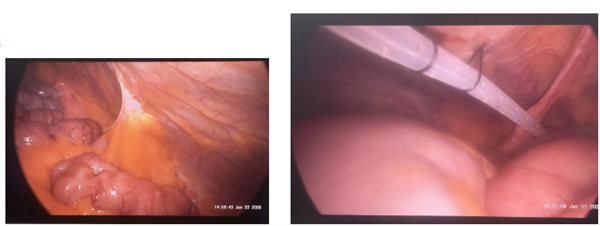

近日,宝鸡市人民医院肾病内科联合泌尿外科、麻醉手术科,成功为一名伴有复杂腹部手术史的终末期肾病(尿毒症)患者实施腹腔镜下腹膜透析置管术。该手术在宝鸡地区尚属首例,标志着我院在终末期肾脏病替代治疗领域实现新突破,为既往有腹部手术史、腹腔条件复杂的患者提供了更安全、更精准的腹膜透析通路建立方案。

本次手术的成功开展,得益于多学科协作(MDT)模式的有效实践。术前,肾病内科、泌尿外科及麻醉手术科专家对患者进行了全面评估;术中,在麻醉科团队的安全保障下,肾病内科与泌尿外科团队借助腹腔镜提供的清晰视野,精细分离腹腔粘连,将导管末端精准置入盆腔理想位置,显著降低了肠管损伤、出血等风险。该微创术式具有操作简便、安全性高、创伤小、恢复快等优势,但对技术操作要求较高。